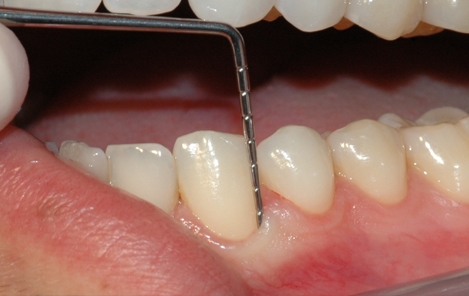

Tannkjøttet og tennenes benfeste blir vurdert